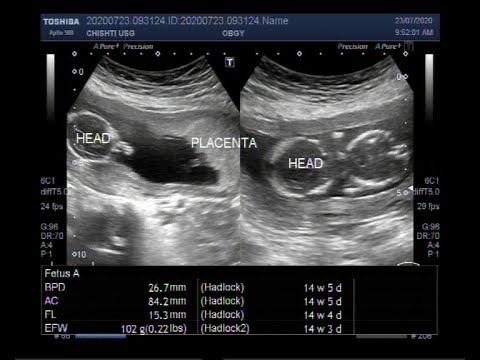

Of all pregnancies approximately 3 of them will result in a missed miscarriage. A little pregnancy update. The ultrasound scan may show.

A miscarriage often occurs very early in the pregnancy often without any alteration of the menstrual cycle and. Falling levels of hCG human chorionic gonadotropin a hormone thats made during pregnancy alongside an ultrasound that shows an empty gestational sac or no fetal heartbeat may also lead to a miscarriage diagnosis. This finding may be titled an early pregnancy failure Most miscarriages occur in the first trimester before the pregnancy has entered the 12th week.

Like most expectant parents they couldnt wait to see the first glimpse of their little one. Ultrasound diagnosis of miscarriage should only be considered when either a mean gestation sac diameter is 25 mm with no obvious yolk sac or a fetal pole with a crown rump length of 7 mm without evidence of fetal cardiac activity. Im so sorry and really hope its a mistake and that youre still pregnant but there is a high chance of miscarriage in very early pregnancy such as yours.

But one look at the screen told Emily something wasnt right. Alicia Gatz who has been a sonographer for the past. Transvaginal ultrasound is the mainstay in the diagnosis of miscarriage.